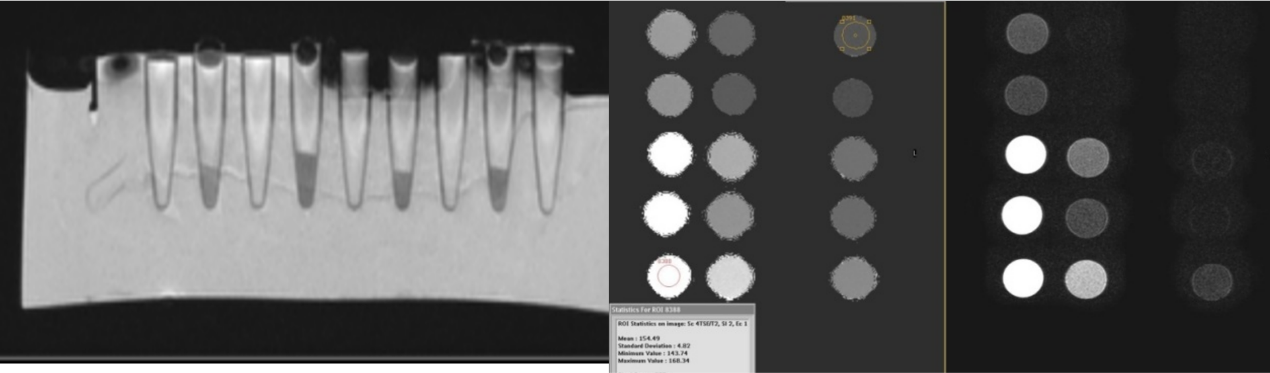

对于模体成像,可支持的实验和可达到的指标为:

w模体定量测定:微米显示

w磁共振成像序列设计及验证:不同技术的对比成像